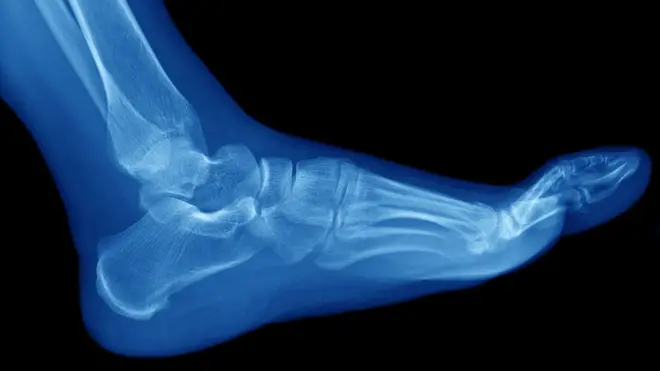

Dolor, rigidez, hinchazón de algunas articulaciones... todos estos son síntomas que comparten la artritis y la artrosis en distinta medida pero, a pesar de lo que mucha gente cree, no son la misma enfermedad.

De hecho, las similitudes se reducen a algunos de sus síntomas y a que ambas patologías afectan a las articulaciones.

- Es una enfermedad crónica no autoinmune que consiste en el desgaste progresivo e irreversible de las articulaciones.

- Ataca al cartílago.

- Su principal síntoma es la rigidez y, aunque puede causar inflamación, no es lo más común.

- Además de dolor intermitente en la articulación, no se presentan otros síntomas en el resto del cuerpo.

- El dolor empeora con la movilidad.